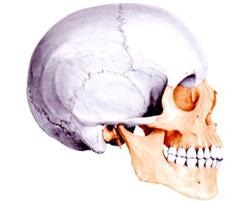

A szerkezet a koponyacsontok

A koponyacsontok képződött lapos, tagjai kompakt anyag, és egy szivacs (diploe). Részéről az agy lemez egy ilyen anyag nagyon törékeny, és könnyen törik a sérülések. A csonthártya csatlakozik a csontok az ízületek, a alkotó más részein a subperiosteal tér van, amelynek egy laza szerkezetű. Belülről a kemény héj működik az agy.

Típusai koponya kapcsolatok

A fő típusú csont ízületi neyrokraniuma - egy syndesmosis. A legtöbb ilyen fúziók képviseli csipkézett varratok; csak közötti időbeli és parietális csontjait halad pehely varrat. Arc koponya lapos hegek. Anatómiailag a varrat gyakran nevezik a nevét segítségével csatlakoznak a csontjai alkotják a koponya. Vegyület koponya csont tartalmaz egy sagittalis varrat (gőz alkalmazásával összeköti a falcsont a koponya), koronális (frontális és parietális összeköti csontok) és lambdoid (összekötő occipitalis és parietális csontjait).

A fejlesztés a koponya egyedfejlődés

Perinatális fejlesztés magában foglalja három lépésben: hártyaszerű, porc és a csont. Az első szakasz során két hétig, a második - két hónapos korban a kialakulását az embrió. A sok részén a koponya át a második szakaszban.

Skull származik az első akkord primordia kötőszövetben és a kopoltyú ívek. Mivel a növekedés az agy, idegek és erek van kialakítva körülöttük. A csontok vannak osztva elsődleges (származó kötőszöveti) és másodlagos (származó a porc). Egy bizonyos ponton vannak elváltozások porcok csontosodásának, amelyek nőnek a mélység, és amely egy kompakt szivacsos csont lemez.